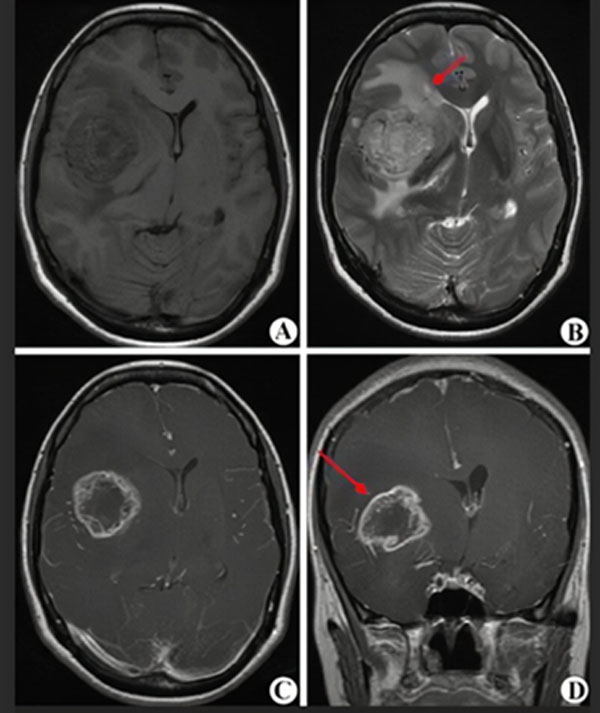

MRI(核磁共振)是一種無創傷的影像學檢查,對腦腫瘤敏感性較高,大約1-2天可以拿到結果,是診斷和評估治療效果的首選。但準確性只有80%-90%,不能作為確診的最終依據。

(圖A-D顯示為高級別膠質瘤的核磁表現,紅箭頭指示腫瘤所在)

膠質瘤最終確診還要依靠立體定向穿刺或開顱手術等有創操作,取得病變組織,由病理科醫生確認病變是否為膠質瘤以及膠質瘤的級別,這一過程大約需要7-10天。